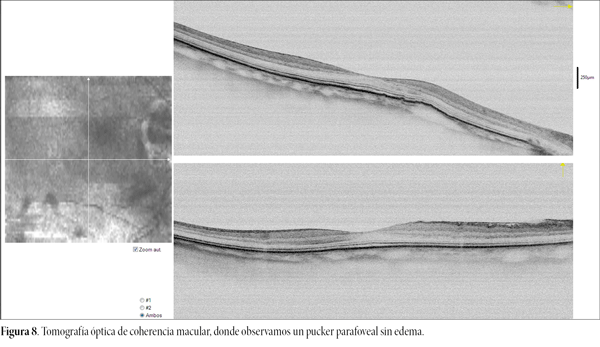

La agudeza visual del ojo derecho sin corrección previa a la cirugía correspondía a LogMAR 1,33. Al examen con refractometría reveló una agudeza visual mejor corregida de LogMAR 0,1 y una refracción de -5,75 D esfera y -1,00 D cilindro a 12° (OI, cilindro -0,50 a 165°). Los estudios prequirúrgicos —incluidos análisis de respuesta ocular (fig. 4), evaluación de ojo seco (fig. 5), topografía corneal y paquimetría (fig. 6)— se hallaron dentro de parámetros normales. La cámara Scheimpflug mostró alteración anatómica del segmento anterior, caracterizadas por las hebras y la catarata piramidal (fig. 7). Además se realizó una tomografía óptica de coherencia siendo el de papila normal pero en el estudio macular se observó un pucker parafoveal sin edema (fig. 8).

Figura 8. Tomografía óptica de coherencia macular, donde observamos un pucker parafoveal sin edema.